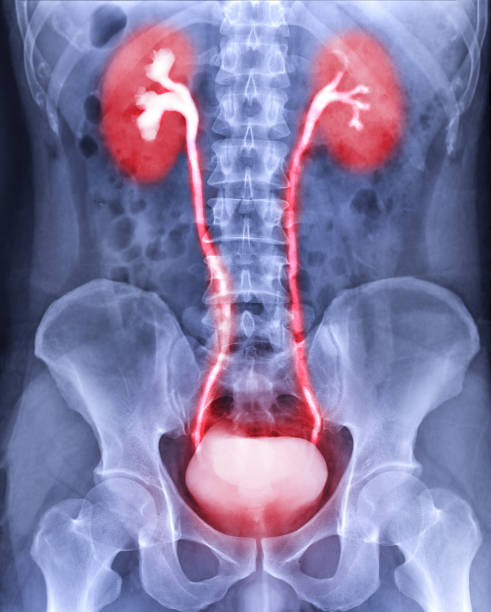

방광암은 초기 증상이 미미하게 나타나기 때문에, 정기적인 건강 검진을 받는 것이 중요합니다. 방광암의 조기 발견을 위해 소변검사, 방광 내시경검사 등의 검사를 시행할 수 있습니다. 이를 통해 환자의 건강 상태를 파악하고, 조기 발견 및 치료로 환자의 생존율을 높일 수 있습니다.

혈뇨

환자는 소변에 피가 섞일 수 있습니다. 이는 방광암으로 인해 생길 수 있는 출혈의 결과입니다.